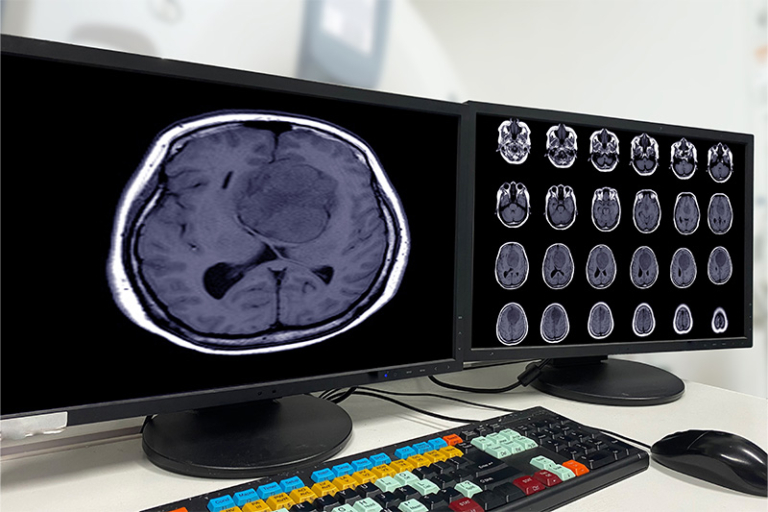

這項國際研究共分析了來自33個西方國家,共17萬名50歲以上參加者的數據,當中包括了逾40萬份記憶測試的分數,和1.5萬張腦部磁力共振的掃瞄數據。結果發現,教育程度愈高的人,晚年的記憶力表現就愈理想,而且顱內體積及記憶相關腦區的體積亦比較大。然而,無論測試者的學歷高與低,其大腦結構的退化速度均沒有明顯分別,反映出教育本身並不能減緩大腦結構的退化速度。那為何高學歷人士,老年時比低學歷人士較少患上腦退化相關症狀?研究團隊進一步解釋,這或與先天因素有關。

研究人員共邀請了1,289人進行實驗,平均年齡為64歲。在研究開始前,團隊會為參加者量度BMI指數及腰圍,並於6年後再邀請他們進行磁力共振(MRI)腦部掃瞄,以量度他們大腦皮層區域的厚度、整體大腦體積及其他因素。